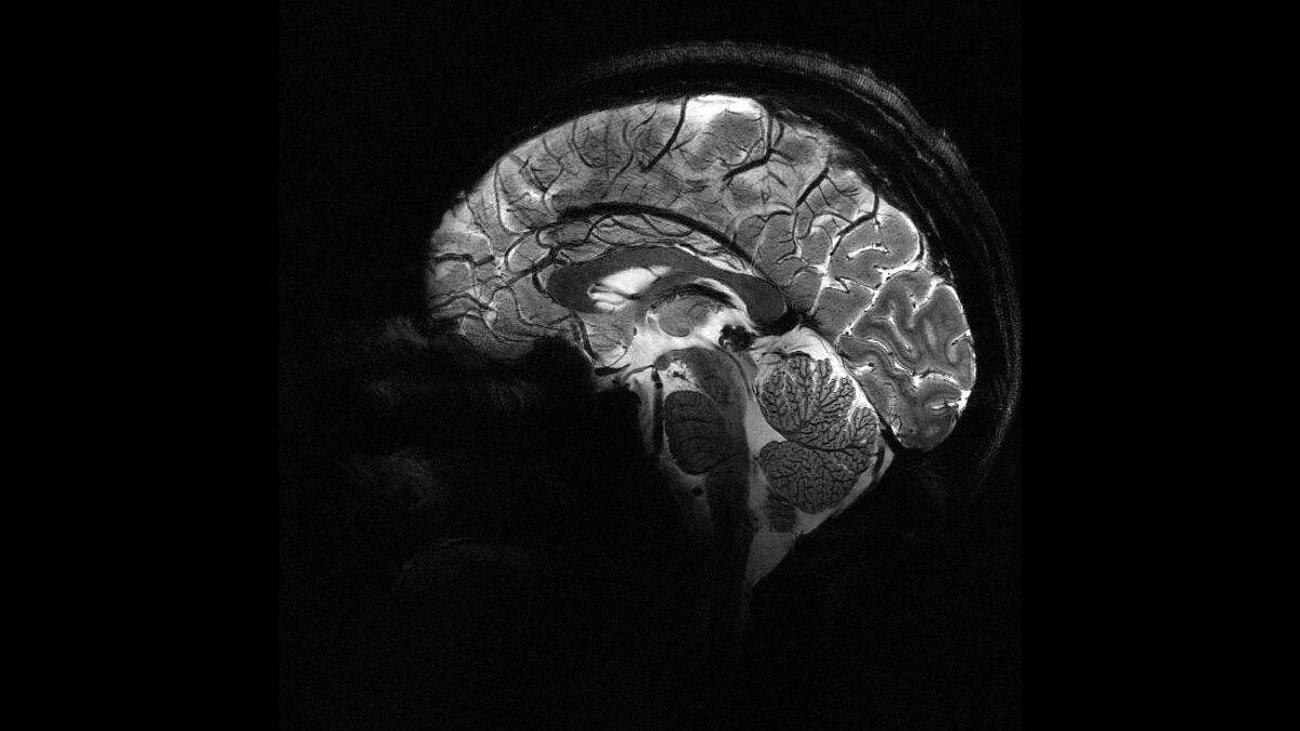

De Iseult MRI-scanner in Frankrijk weet in vier minuten tijd superscherpe beelden te schieten.

Naast de scherpte van de beelden die de zogenoemde Iseult MRI-scanner schiet, zijn er nog wat voordelen aan de krachtpatser. Zo neemt het apparaat een stuk minder lang de tijd dan conventionele MRI-scanners: in slechts vier minuten klaart hij de klus. Ook is de opening wat groter – een diameter van 90 centimeter in plaats van de gebruikelijke 60 tot 70 centimeter. Comfortabeler voor de patiënt.

Twintig jaar geleden startte Frankrijk met de bouw van de Iseult MRI-scanner. Om het apparaat te testen, scande het een paar jaar terug eerst pompoenen. Inmiddels hebben tientallen menselijke vrijwilligers in de scanner gelegen. Het apparaat moet ons uiteindelijk meer inzicht geven in onder andere de werking van het brein, ons bewustzijn, neurodegeneratieve ziektes zoals de ziekte van Alzheimer en Parkinson, en het effect van medicijnen in de hersenen.